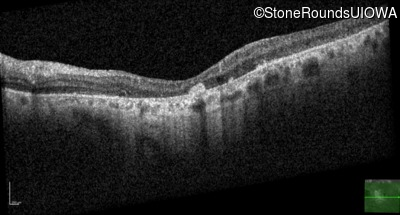

Optical Coherence Tomography - Right - 20/100

Exemplar / OCT Stack

OCT Stack

Optical Coherence Tomography - Left - 20/100

Infrared Fundus Photograph - Right - 20/100

Exemplar

Infrared Fundus Photograph - Left - 20/100